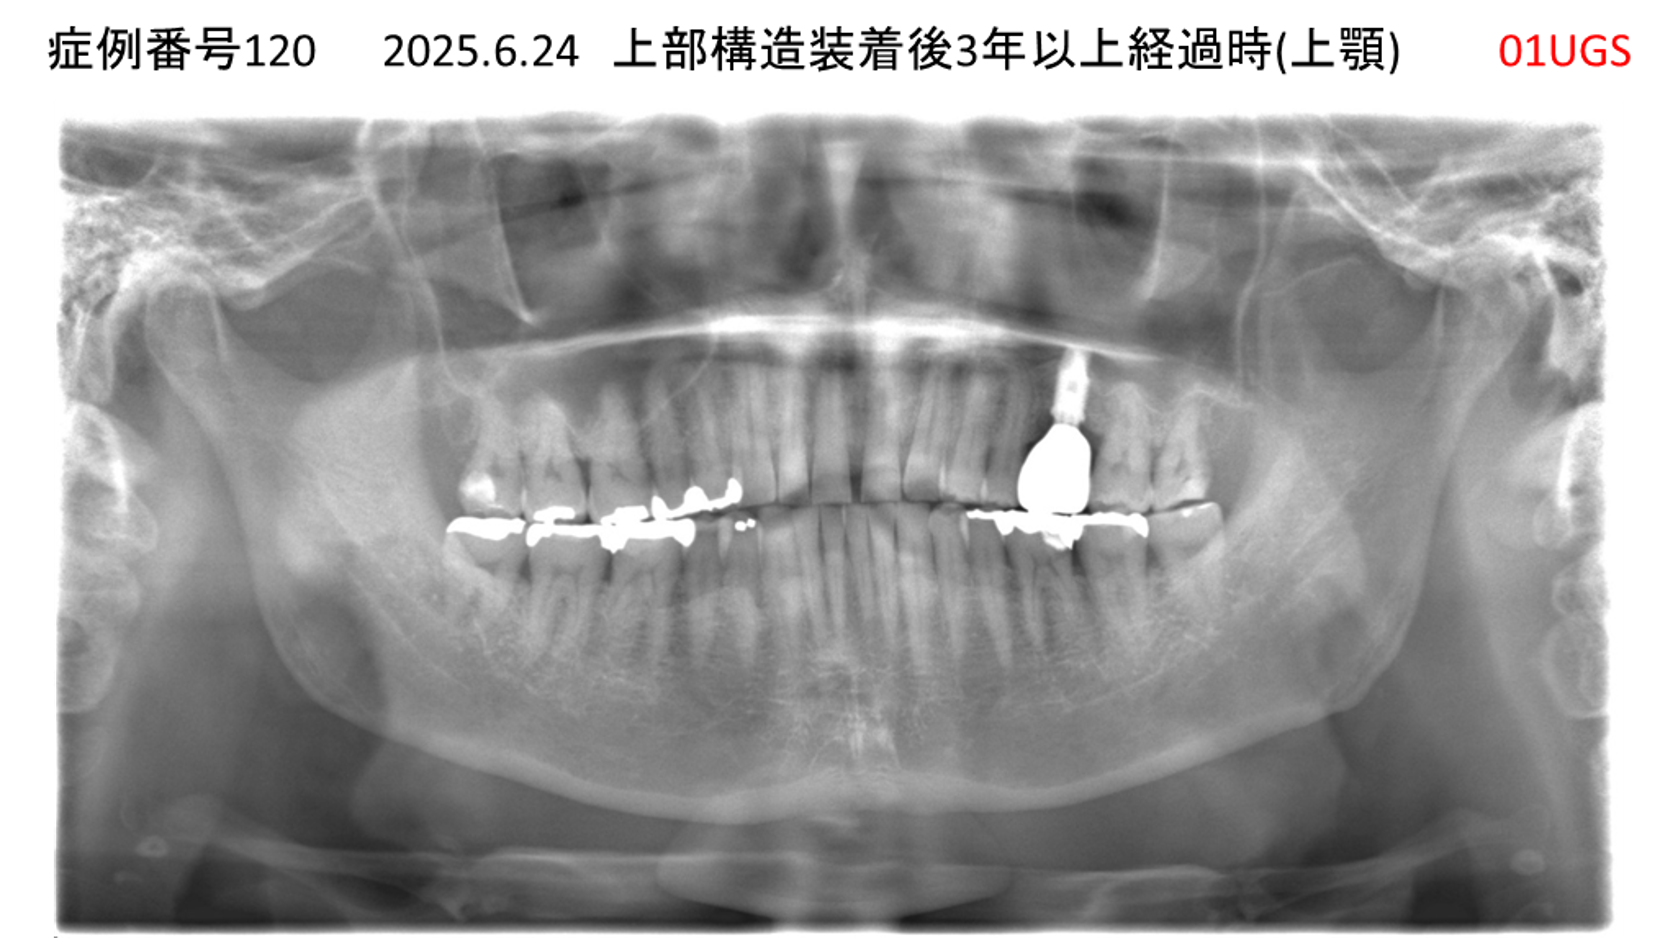

上の前歯が揺れてきた患者様のインプラント症例

| 治療名称 |

インプラント |

| 治療費用 |

390万円+税 |

| 治療期間 |

6か月 |

| 患者さんの症状(主訴) |

上の前歯が揺れてきた。固いものが食べられない。 |

| 治療内容 |

サイナスリフト、抜歯即時インプラント |

| 治療結果 |

上の前歯の揺れが収まった。食べ物がおいしい。 |

| 治療の注意点(リスク/副作用) |

インプラントが壊れたら再治療が必要 |